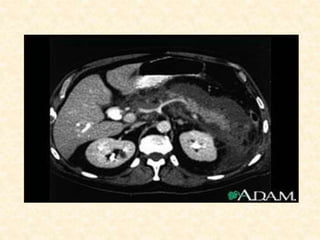

Computer Tomography (CT)

• Imaging modality of choice for diagnosis, determining

severity, and identifying complications

• Sensitivity: 90% for diagnosis of acute pancreatitis

• Specificity: 98-100%

• Not necessary for mild acute pancreatitis; however is

useful to rule out other abdominal processes presenting

with abdominal pain.

• Mild disease: no abnormalities, diffuse enlargement of

pancreas, loss of normally sharp border, homogenous

attenuation, inflammatory stranding in peripancreatic fat

and adjacent soft tissue, fluid collections, pseudocysts,

pancreatic necrosis

• Necrotizing pancreatitis:

Non-enhancement of ≥ 1/3 of pancreas or

>3cm of non-enhancement of the

pancreas on dynamic, IV contrast-

enhanced CT.

If > 30% gland involved, sensitivity

approaches 100%